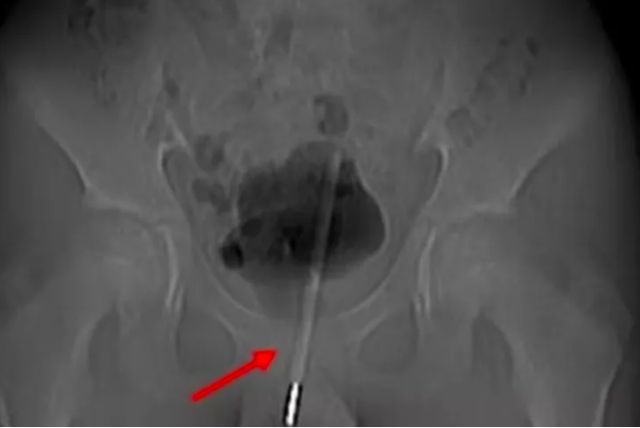

Röntgenler, termometrenin idrar yoluna o kadar sokulduğunu ve çocuğun mesanesine girdiğini ortaya çıkardıktan sonra, doktorlar anahtar deliği ameliyatı kullanarak termometreyi çıkarmaya karar verdiler. Asian Journal of Surgery'de vakayı detaylandıran ürologlar, mesaneye giden dokuda küçük bir cerrahi delik açtıklarını ve ardından termometreyi doğru konuma getirerek onu çıkarmak için küçük aletler kullandıklarını söylediler. Ameliyatın başarısına rağmen, çocuğun deneylerinden dolayı uzun vadeli herhangi bir komplikasyon yaşayıp yaşamadığına dair bir açıklama yapılmadı.